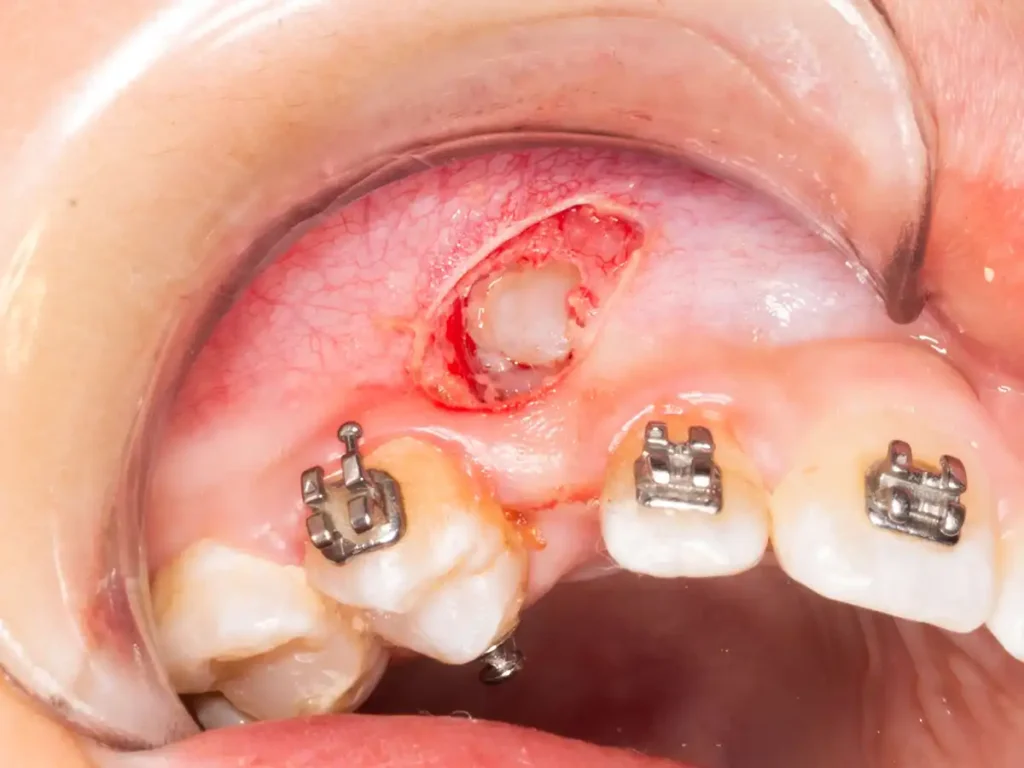

Cirugía de exposición y tracción ortodóntica de canino retenido

Una vez evaluada la posición y profundidad del canino retenido, se indicó su exposición quirúrgica y la adhesión inmediata del botón de tracción ortodóntica en el mismo acto operatorio. Esta secuencia permite evitar pérdidas de tiempo entre la exposición y el inicio del movimiento dentario.

La apertura quirúrgica se realizó con electrocirugía, permitiendo un campo operatorio limpio y buen control visual. Luego se instaló la mecanoterapia inicial para comenzar la rotación coronaria y orientar el canino hacia una posición más favorable dentro de la arcada.